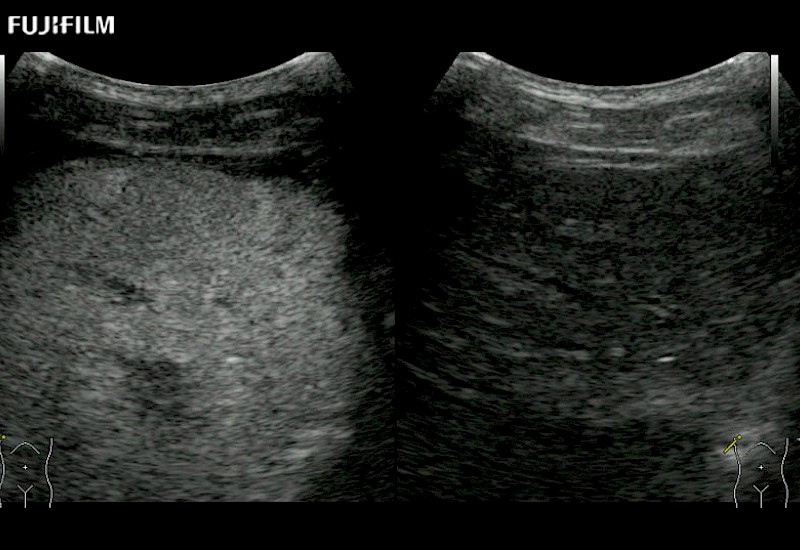

Learn moreFujifilm Healthcare continues to listen to the experts, our neurosurgeons, by developing an ultrasound system specifically designed for the Operating Room.

Guidance is the fundamental purpose for all of our surgical ultrasound technology. Fujifilm Healthcare is committed to designing tools that help neurosurgeons navigate inside the human body and provide the necessary information to immediately make critical surgical decisions.

With the ARIETTA Precision the next level of surgical ultrasound is here.